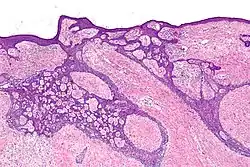

![Fibroepitheliomatous pattern (anastomosing basaloid epithelial strands enclosing round islands of fibrous stroma)[36]](./_assets_/Micrograph_of_basal-cell_carcinoma_with_fibroepitheliomatous_pattern.jpg)